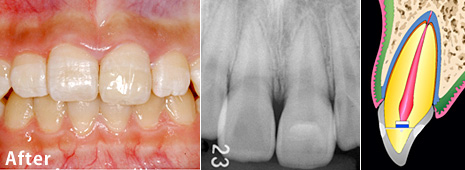

歯冠破折の治療例 その1

Before

After

主訴歯冠破折

年齢・性別12歳 男性

治療方法見えていた歯髄の表層をとり(断髄し)、歯髄の傷が治りやすい薬で傷口を保護しました。その後、折れた破折片を、修復材にてもとの歯に接着しました。